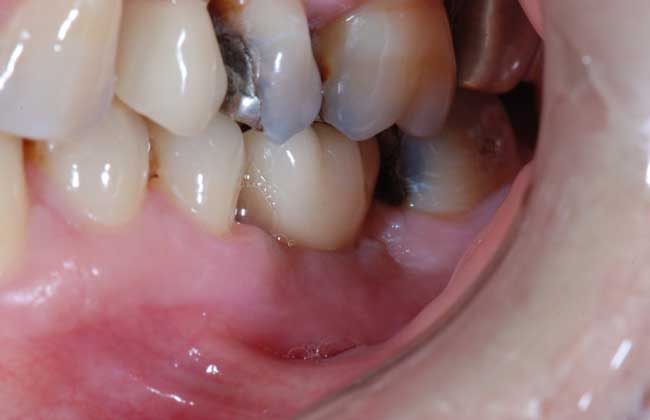

2、牙龈增生:种植牙由于基台穿龈过少或基台与桥架连接不良造成局部卫生状况差,长期的慢性炎性刺激可致牙龈增生。

5、导致出血:种完牙齿后应该是没有出血的,如果牙医在粘骨膜剥离时损伤大或粘膜下剥离广泛,尤其是术后压迫不良,均易发生粘膜下或皮下出血。